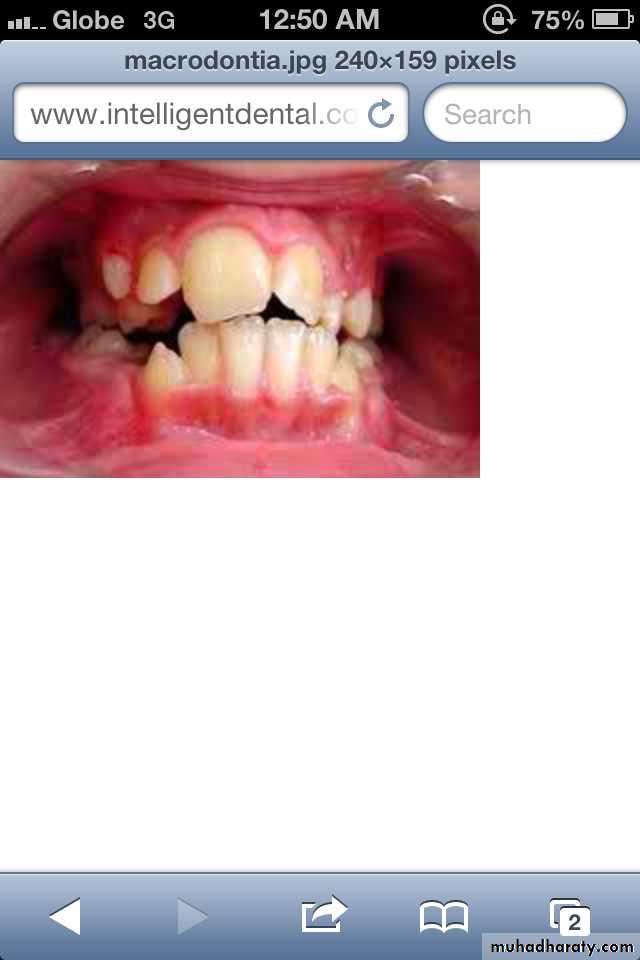

Macrodontia: the teeth are larger than normal, or the teeth are of normal size but occur in smaller than normal jaws.

Normal or slightly larger than normal teeth in small jaws results in:

crowding of teethmalocclusion

impaction may occur.

(2) Relative Generalized Macrodontia